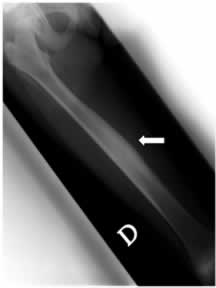

L'ecografia e la radiografia dell'arto inferiore destro mostrano rispettivamente un minimo versamen to articolare a livello della coxo-femorale e un aspetto del femore, sempre a destra, di marcato is pessimento della corticale ossea, come da reazione periostale, con una relativa iperdiafania della spongiosa. (figura 2)

Figura 2: radiogramma del femore che mostra, al III medio, marcato aumento di spessore della corticale ossea sul versante interno

Questi reperti associati al dato scintigrafico dell'anno precedente di ipercaptazione lungo tutto il femore, con artrite e risposta ai FANS, orientano verso un quadro di periostite ricorrente.